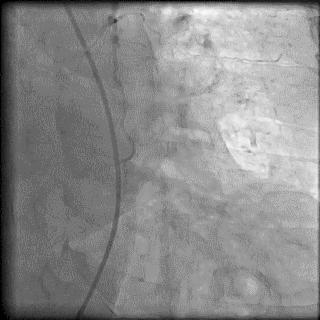

食管后起源右锁骨下动脉是一种较为少见的变异类型,发生率约为0.5%,食管后起源右锁骨下动脉是在右颈总动脉、左颈总动脉和左锁骨下动脉发出后直接起源于主动脉,随后绕行于食管的后方(图4)。由于食管后起源右锁骨下动脉进入主动脉的位置过于靠后,因此操作导引钢丝时非常容易进入降主动脉,此时前送造影导管至右锁骨动脉在主动脉的入口部,通过逆时针旋转导管使导管尖端指向升主动脉方向后再前送导丝。但即使应用上述方法也很难使导丝到位,大多数情况下不得不更换为对侧桡动脉或股动脉路径。

图4 食管后起源右锁骨下动脉

图5 食管后起源右锁骨下动脉造影导管到位处理:先尝试常用方法,包括选用亲水涂层导丝、前送导丝时患者深吸气以拉直血管、利用造影导管的头端弯曲调整导丝的尖端走向、利用导管和导丝的相对运动前送导丝等等,努力将导丝送入升主动脉